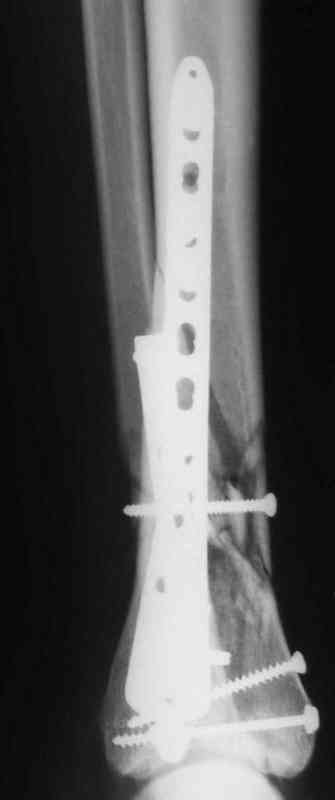

Др. Дрягин в своих случаях показал и правильно подсказывает методику АО, в первую очередь восстановление длины малоберцовой, а потом восстановление суставной поверхности и в зависимости от случая в дистальном эпиметафизе с костной пластикой. Конечно, в идеале, если это возможно, применение современных фиксаторов без открытия места перелома с перкутанными и малоинвазивными пластинами с угловой стабильностью.

Классическая последовательность открытой редукции состоит из следующих этапов: 1-Восстановление длины и фиксация перелома малоберцовой кости

2 - Реконструкция суставной поверхности большеберцовой кости. 3 - Заполнение

метаэпифизарного дефекта свободным костным трансплантатом. 4 - поддерживающая фиксация с помощью накостных пластин.

Да кстати нашёл похожий случай для пилона.Малоинвазивная дистальная пластина LCP у вас я думаю есть опыт их использования ну очень хорошая. Очень стабильно получается.